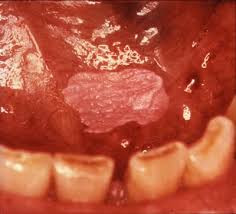

German scientists identified a link between smoking and lung cancer in the late 1920s, leading to the first anti-smoking campaign in modern history, albeit one truncated by the collapse of the Third Reich at the end of the Second World War.[4] In 1950, British researchers demonstrated a clear relationship between smoking and cancer.[5] Scientific evidence continued to mount in the 1980s, which prompted political action against the practice. Rates of consumption since 1965 in the developed world have either peaked or declined.[6] However, they continue to climb in the developing world.[7]